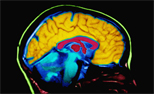

Alzheimer's and the brain

Just like the rest of our bodies, our brains change as we

age. Most of us notice some slowed thinking and occasional

problems remembering certain things. However, serious memory

loss, confusion and other major changes in the way our minds

work are not a normal part of aging. They may be a sign that

brain cells are failing.

The brain has 100 billion nerve cells (neurons). Each nerve

cell communicates with many others to form networks.

Nerve cell networks have special jobs. Some are involved in

thinking, learning and remembering. Others help us see, hear

and smell. Still others tell our muscles when to move.